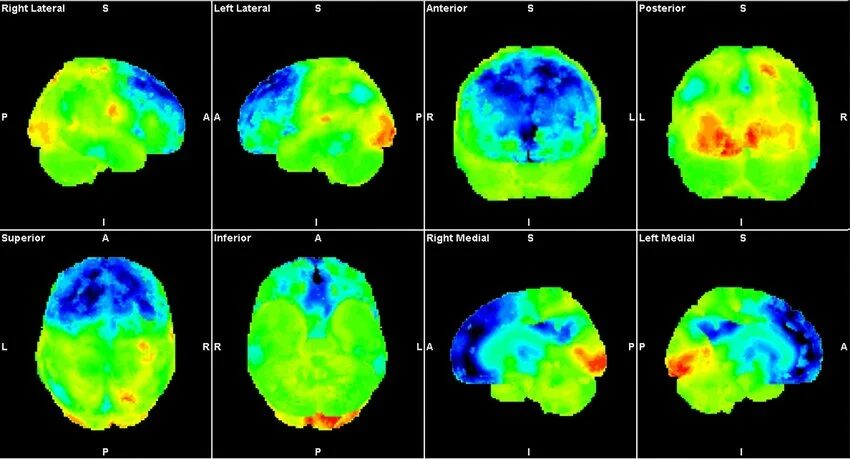

9.脳イメージング革命(1990)

技術:

- MRI

- PET

- fMRI

転換点:精神疾患を脳回路として理解。